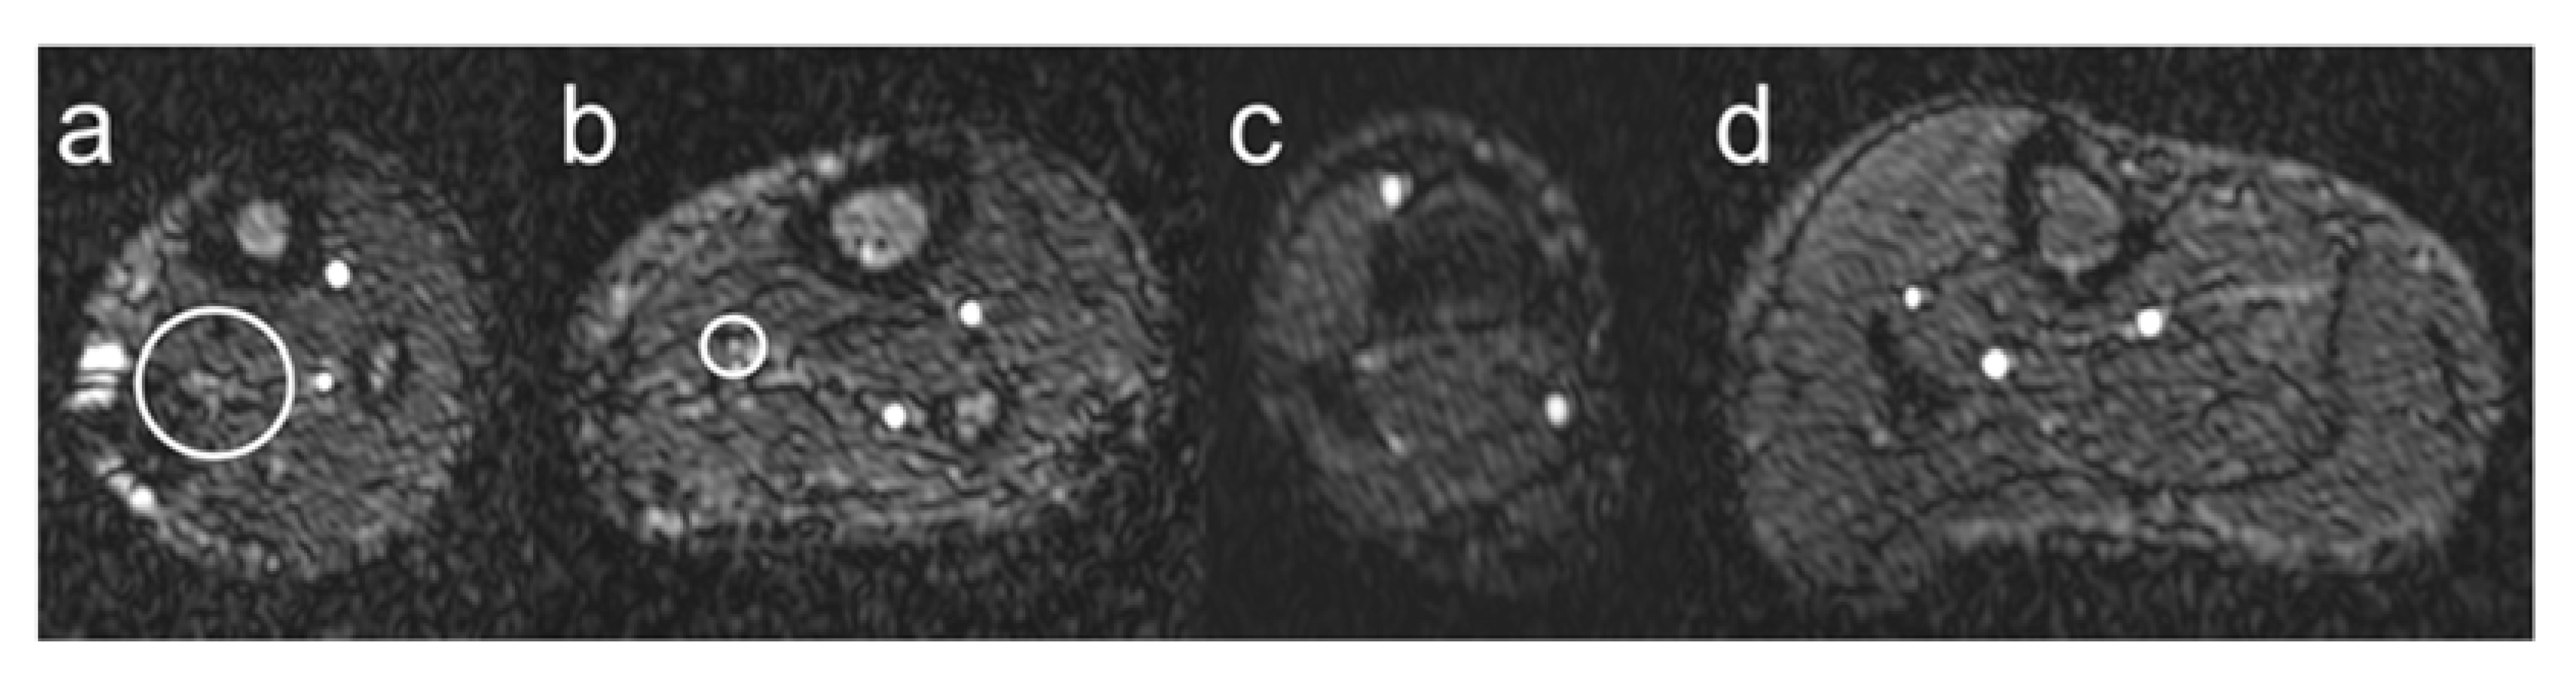

Visualization of ATs, PTs, and FAs was evaluated by assessing continuity, visibility, and edge sharpness using a 1 to 4 grading scale for image quality (Figure 2):

Figure 2.

Vessel visualization. Schematic illustration of the visualization of lower leg arteries based on the grading scoring system introduced in Section 2.3. Grade 1 is shown in panel (a), grade 2 in panel (b), grade 3 in panel (c), and grade 4 in panel (d). The white circles indicate lower leg arteries with barely visible lumen (grade 1) and poorly defined vessel boundaries (grade 2).

- Grade 1: Nondiagnostic, barely visible lumen rendering the segment.

- Grade 2: Fair, ill-defined vessel borders with suboptimal image quality for diagnosis.

- Grade 3: Good, minor inhomogeneities not influencing vessel delineation.

- Grade 4: Excellent, sharply defined arterial borders with excellent image quality for highly confident diagnosis.